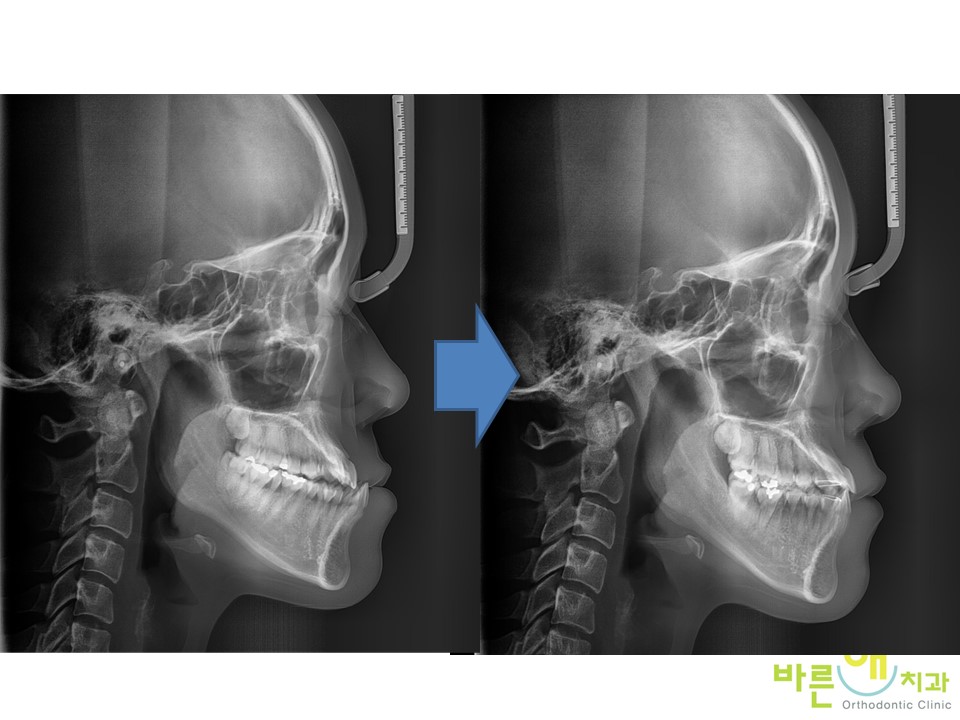

¿·¾ó±¼ ¿¢½º·¹ÀÌ¿¡¼­´Â

ÀÌ·± º¯È­°¡ ÀϾ½À´Ï´Ù.

ÅÎÀ» ÀÚ¸£´Â ¾ç¾Ç¼ö¼úÀÌ ¾Æ´ÏÁö¸¸

Ä¡¾ÆÀÇ º¯È­¿¡ ¸ÂÃç¼­

¾Æ·¡ÅÎÀÇ À§Ä¡°¡

ÈĹæÇϹæÀ¸·Î

º¯È­µÈ °ÍÀ» º¼ ¼ö ÀÖ½À´Ï´Ù.

ºñ¼ö¼ú ÁÖ°ÆÅÎ ±³Á¤Ä¡·á¸¦ ÇÏ´Â

13°³¿ù µ¿¾ÈÀÇ ÁÖ¿ä º¯È­ÀÔ´Ï´Ù.

13°³¿ù µ¿¾ÈÀÇ

ºñ¼ö¼ú ÁÖ°ÆÅÎ ±³Á¤Ä¡·á ÀüÈÄÀÇ

¿·¾ó±¼ ¿¢½º·¹ÀÌ ÀÔ´Ï´Ù.